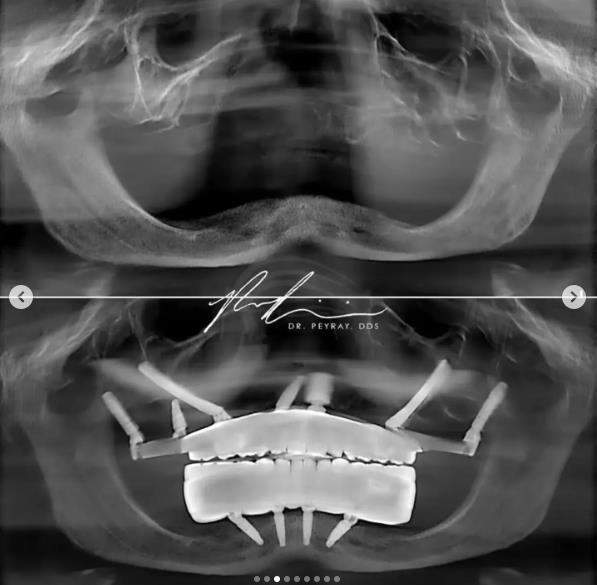

U galeriji pogledajte kakvu je šok transformaciju napravio dr Perman Rejsi:

Stomatolog dr Perman Rejsi iz Sjedinjenih Američkih Država na svom Instagramu podelio je transformaciju jednog pacijenta, a fotografije pre i posle intervencije prikazuju nam jednog mladića.

Bez zuba, sa gotovo „zgužvanim“ donjim delom lica i neverovatnu promenu nakon što su mu ugrađeni implanti. Lice mu je doslovno vraćeno u prirodno i prvobitno stanje i konačno je mogao da se osmehne. Sebi, životu i mnogo lepšoj budućnosti koja ga očekuje.

Dr Pej Rej, kako je poznat na mrežama, pokazao je putem fotografija i video snimaka kako funkcioniše čitava procedura, pa pomenuo koliko je implantologija značajna grana stomatologije. Pogotovo kada su u pitanju ljudi koji su izgubili sve zube. A samim tim i nadu i volju za životom, koje im on, svojim ukmećem i znanjem, vraća.